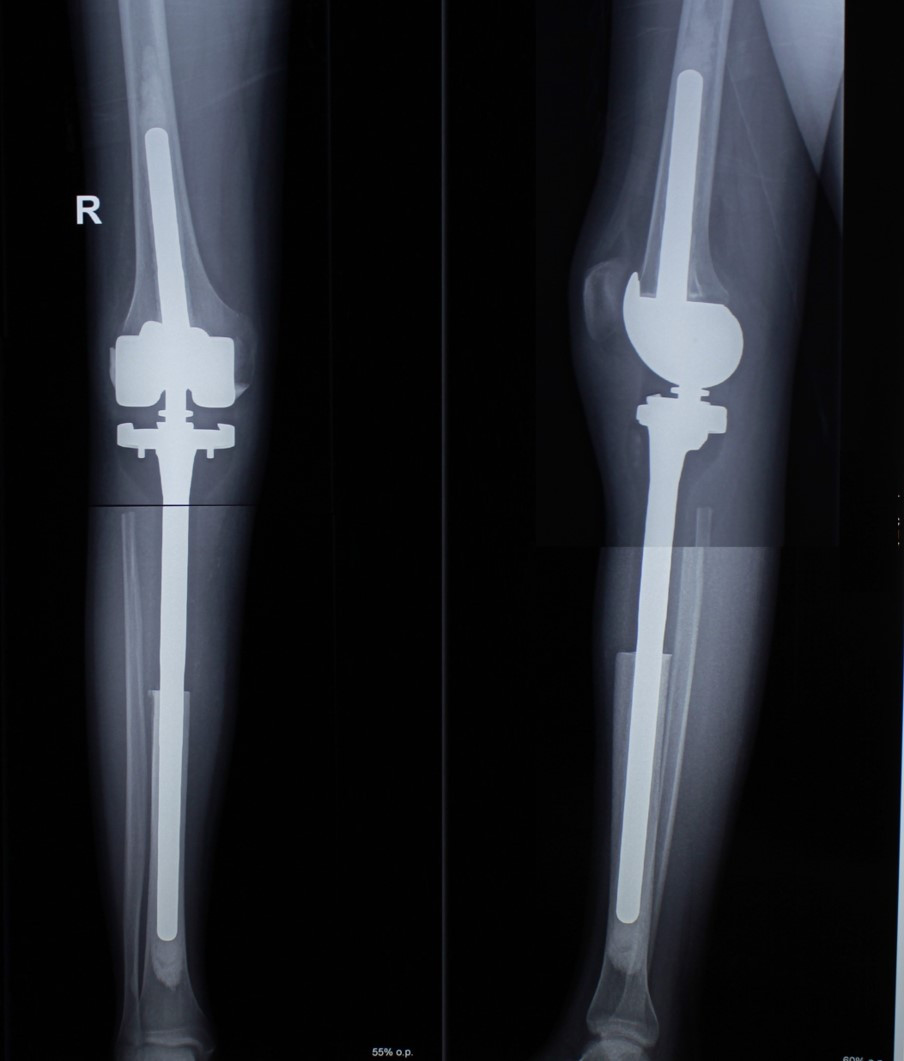

2. Բժշկական տարբեր կենտրոններում հետազոտվելուց հետո՝ 17-ամյա պատանին դիմել է «Նաիրի» ԲԿ։ Համապատասխան հետազոտություններ անցնելուց հետո՝ բուժառուի մոտ հայտնաբերվել է ոլոքի օստեոսարկոմա (ոսկրային քաղցկեղ): Նախավիրահատական բուժում ՝ քիմիոթերապիա, ստանալուց հետո՝ «Նաիրի» ԲԿ ում կատարվել է օրգանապահպան վիրահատություն : Հեռացվել են ծնկահոդն ու ոլոքի վերին երորդականը: Առաջացած դեֆորմացիան շտկել է Եվրոպայից պատվիրված էդոպրոթեզով, որը հնարավորություն է տվել պահպանել վերջույթի գործառույթը՝ քայլել, վազել և այլն։ Հետվիրահատական շրջանում բուժառուն ստացել է քիմիոթերապիա։ Այժմ գտնվում է բժիշկների հսկողության ներքո։

Վիրահատությունից առաջ

Վիրահատությունից հետո